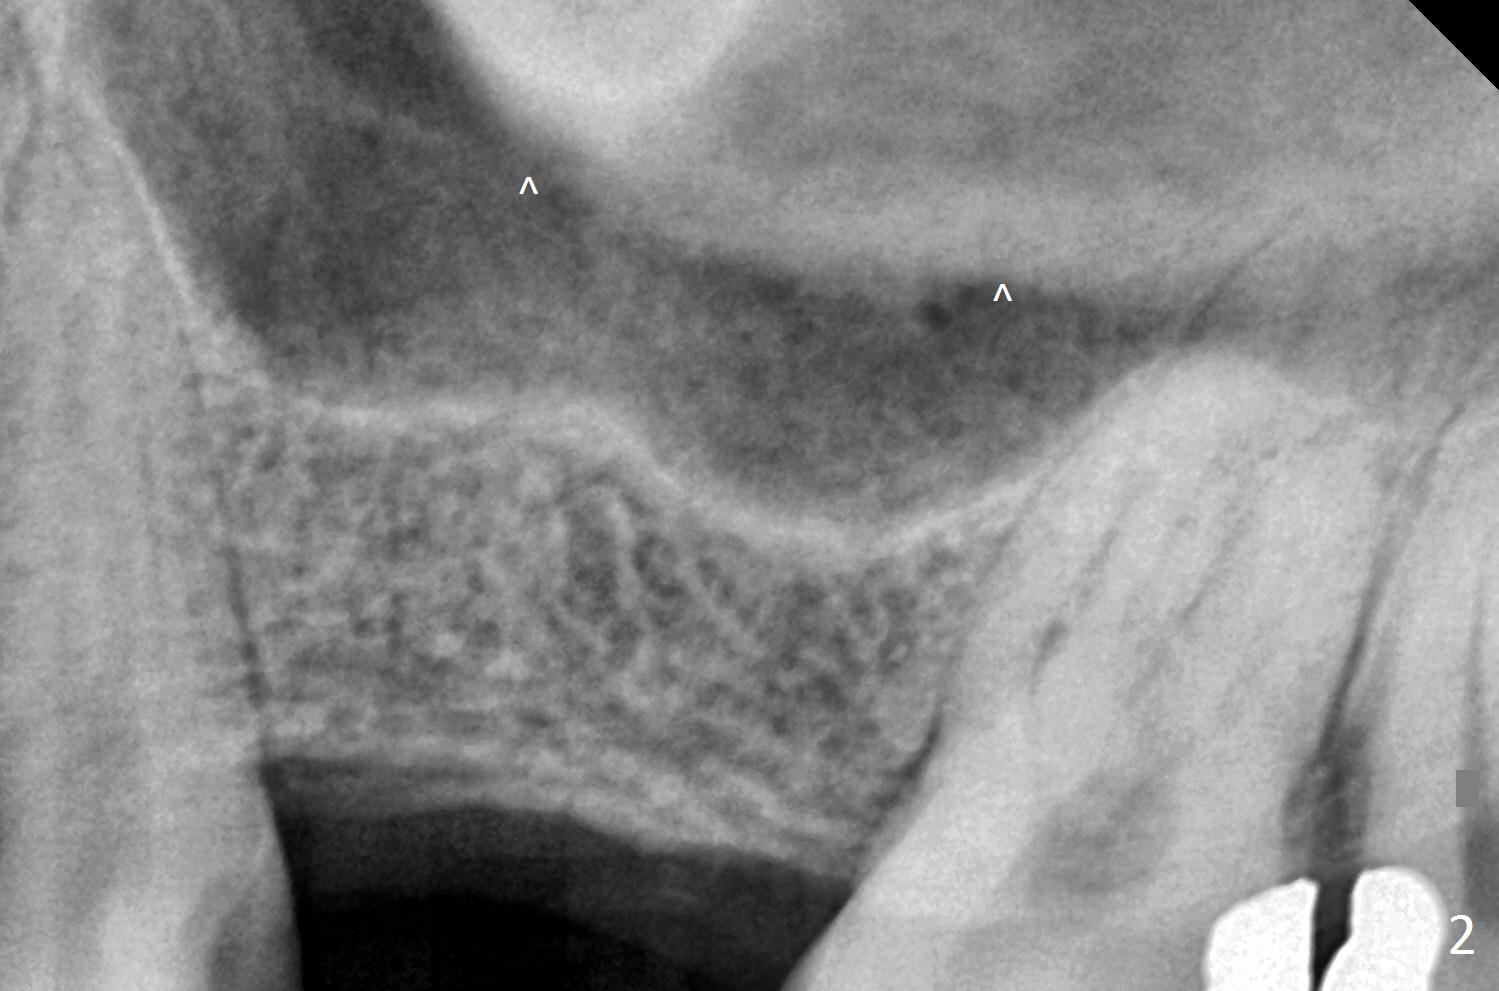

A 47-year-old man agrees implant at #14 (Fig.1).  He worries about the bone height.  There appear to be 2 layers of the sinus floor (Fig.1,2 (arrowheads: upper one)).  The horizontal plate of the palate is indicated by *.  An IBS implant will be placed between the 2 layers of the sinus floor as shown in Fig.3.  Osteotomy is initiated with Magic Split, followed by Magic Expanders (initial depth 9 mm gingival level) or Magic Lifter.  Before placing the implant, insert PRF and Allograft with a condenser with a stopper.